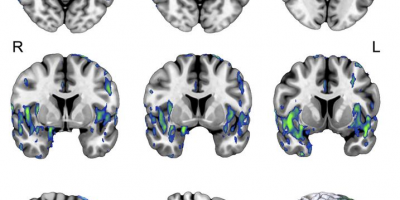

Die Gehirne von COVID-19-Patienten wiesen einige der gleichen pathologischen Veränderungen auf, die bei der Alzheimer-Krankheit beobachtet werden, was die Gedächtnisprobleme von Menschen mit langer COVID-Erfahrung erklären könnte….

Die Studie … verbindet die Entzündungsreaktion, die bei einer SARS-CoV-2-Infektion auftritt, mit Wegen, die eine Tau-Hyperphosphorylierung verursachen, die typischerweise mit #Alzheimer in Verbindung gebracht wird. Die Daten deuten auch auf eine Rolle für den undichten Ryanodin-Rezeptor 2 (RyR2) in der Pathophysiologie der SARS-CoV-2-Infektion hin.

“Die große Stärke der Arbeit ist, dass sie Anomalien in mehreren Molekülen identifiziert haben, die dazu beitragen, die neurogliale Dysfunktion bei diesen Patienten auf biochemischer Ebene zu charakterisieren”, so Avindra Nath, MD, vom National Institute of Neurological Disorders and Stroke.